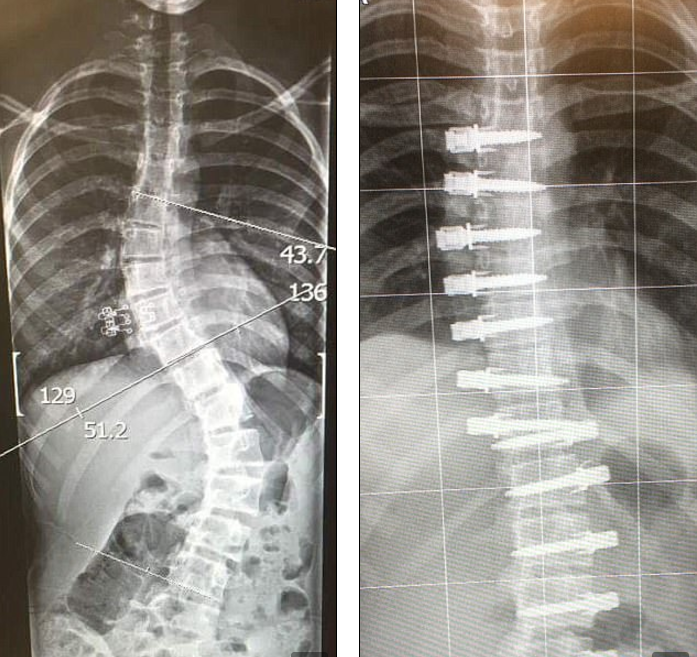

英國體壇少女脊骨驚變S型,以為天塌下來?用尼龍繩即可拉返直。但這先驅手術並不便宜,父母須按屋及預支退休金,才籌足150萬港元送愛女到美國做手術,保住她的健康與體育夢。

Ella Tomlinson(14歲)是赫特福德郡曲棍球及英式籃球代表隊成員,18個月前一次穿露腰短衣,竟揭露了晴天霹靂病徵:腰脊扭成S狀。經診斷證實患嚴重脊柱側彎,必須施手術矯正。通常接受脊柱穩定植入物,如固定桿、椎弓根螺釘與連接鋼片。但其時Ella才12歲,植入鋼片等入侵性手術必影響她的發育,運動員生涯亦就此告終。

美國則有先進手術,以有彈性的尼龍繩代替金屬片,穩固矯正脊椎之餘,結構亦隨骨骼成長而作出調整,更大優點是無礙患者的機能與體力。缺點卻是極昂貴,醫保更免問。Tomlinson夫婦最終以按揭貸款、預支退休金才湊足赴美治療的150萬港元費用。